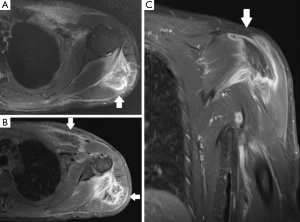

In comparison to US, MR imaging is less operator dependent, facilitates a more global assessment of the entire chest, and enables better differentiation of tendon tissue from tissues affected by trauma. It is the imaging method of choice when the diagnosis is not clear, and may avoid surgical delays particularly when surgery is indicated. Different MR imaging protocols may be suitable for imaging of thoracic wall muscles. T1-weighted sequences are good for evaluating the anatomy but lack sensitivity in the detection of fluid, with exception of some chronic hematomas due to very short T1 values (and corresponding brightness on T1-weighted images). Fluid-sensitive MR imaging sequences such as STIR, T2-weighted imaging with fat saturation, and proton-density—weighted imaging with fat saturation are essential for detecting increased fluid signal intensity induced by a traumatic process.

A normal pectoralis major tendon should have uniform low signal intensity on MR imaging. Like US (34), tears of the pectoralis major tendon seen on MR imaging exhibit different degrees of tendon abnormality, depending on the degree of injury. A grade I strain of the muscle belly will have feathery intramuscular fluid-sensitive signal intensity, which represents oedema and/or haemorrhage. Grade II injury will appear as a partial tear with an intramuscular hematoma, while grade III injury has a complete tear with possible retraction (Figures 11-13). As a matter of fact, a partial tear involving only the posterior sternal segments, the anterior clavicular head and tendon will be intact, with the long head of the biceps tendon in place. With complete tears involving both the sternal head and the clavicular head, however, there will be disruption of the entire tendon, with anterior displacement of the long head of the biceps tendon (35).

The rotator cuff stabilizes the humeral head in the glenoid cavity and comprises the supraspinatus, infraspinatus, teres minor and the subscapularis muscles and tendons. They all originate in the scapula (the supraspinatus on the supraspinous fossa, the infraspinatus on the infraspinous process, the teres minor on the posterior surface of the scapula and the subscapularis on the subscapular fossa), and their tendons insert on the humerus (the first three on the greater tubercle of the humerus, and the subscapularis on the lesser tubercle). Tears of the rotator cuff are more common in older patients, generally associated with degenerative changes (the supraspinatus being the most commonly involved). However, acute traumatic tears can also occur in young and athletic individuals. Lesions usually affect the humeral insertion of the rotator cuff tendons, but can also more rarely affect their muscular origins in the scapula. Clinical examination and plain radiographs are almost never helpful in predicting rotator cuff muscle tears immediately after trauma, whereas MRI has proven its usefulness in the assessment of these lesions (Figure 14). Patients with injuries at the muscle origin or belly are treated conservatively (38).